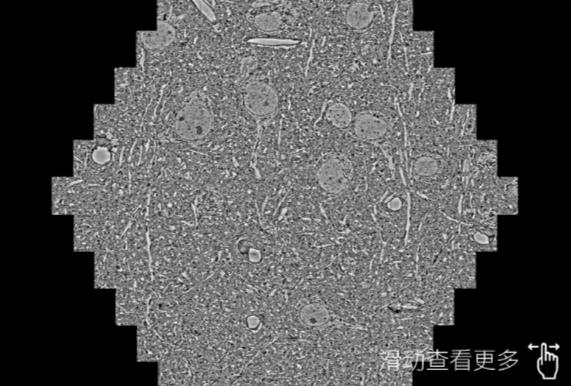

鼠脑切片。左图使用舟山蔡司舟山扫描电镜MultiSEM706对165μmx143pm面积区域成像,耗时仅需1.5秒。右图为鼠脑切片中30μm区域放大效果。样品由芝加哥大学B.Kasthuri提供。

使用蔡司高速舟山扫描电镜MultiSEM对1mm²人脑皮层组织进行高分辨成像,并对其中的各种细胞结构进行三维重构分析。左图展示了2x3mm²组织平面中锥体神经元的三维重构效果。右图显示了局部体积神经元三维重构。图像由哈佛大学chtman实验室提供,渲染图由D. Berger 制作。